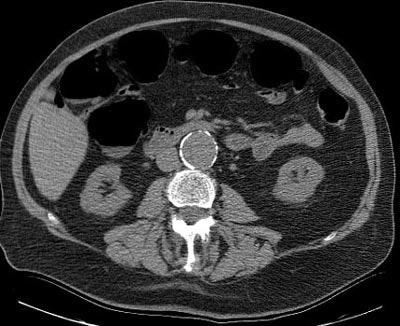

![]() |

| Sixty-eight-year-old man with history of colonic polyps presented for fiberoptic colonoscopy and concurrent virtual colonoscopy. He was found to have a 4-cm abdominal aortic aneurysm as a new incidental finding, and subsequently underwent aortofemoral bypass grafting. |